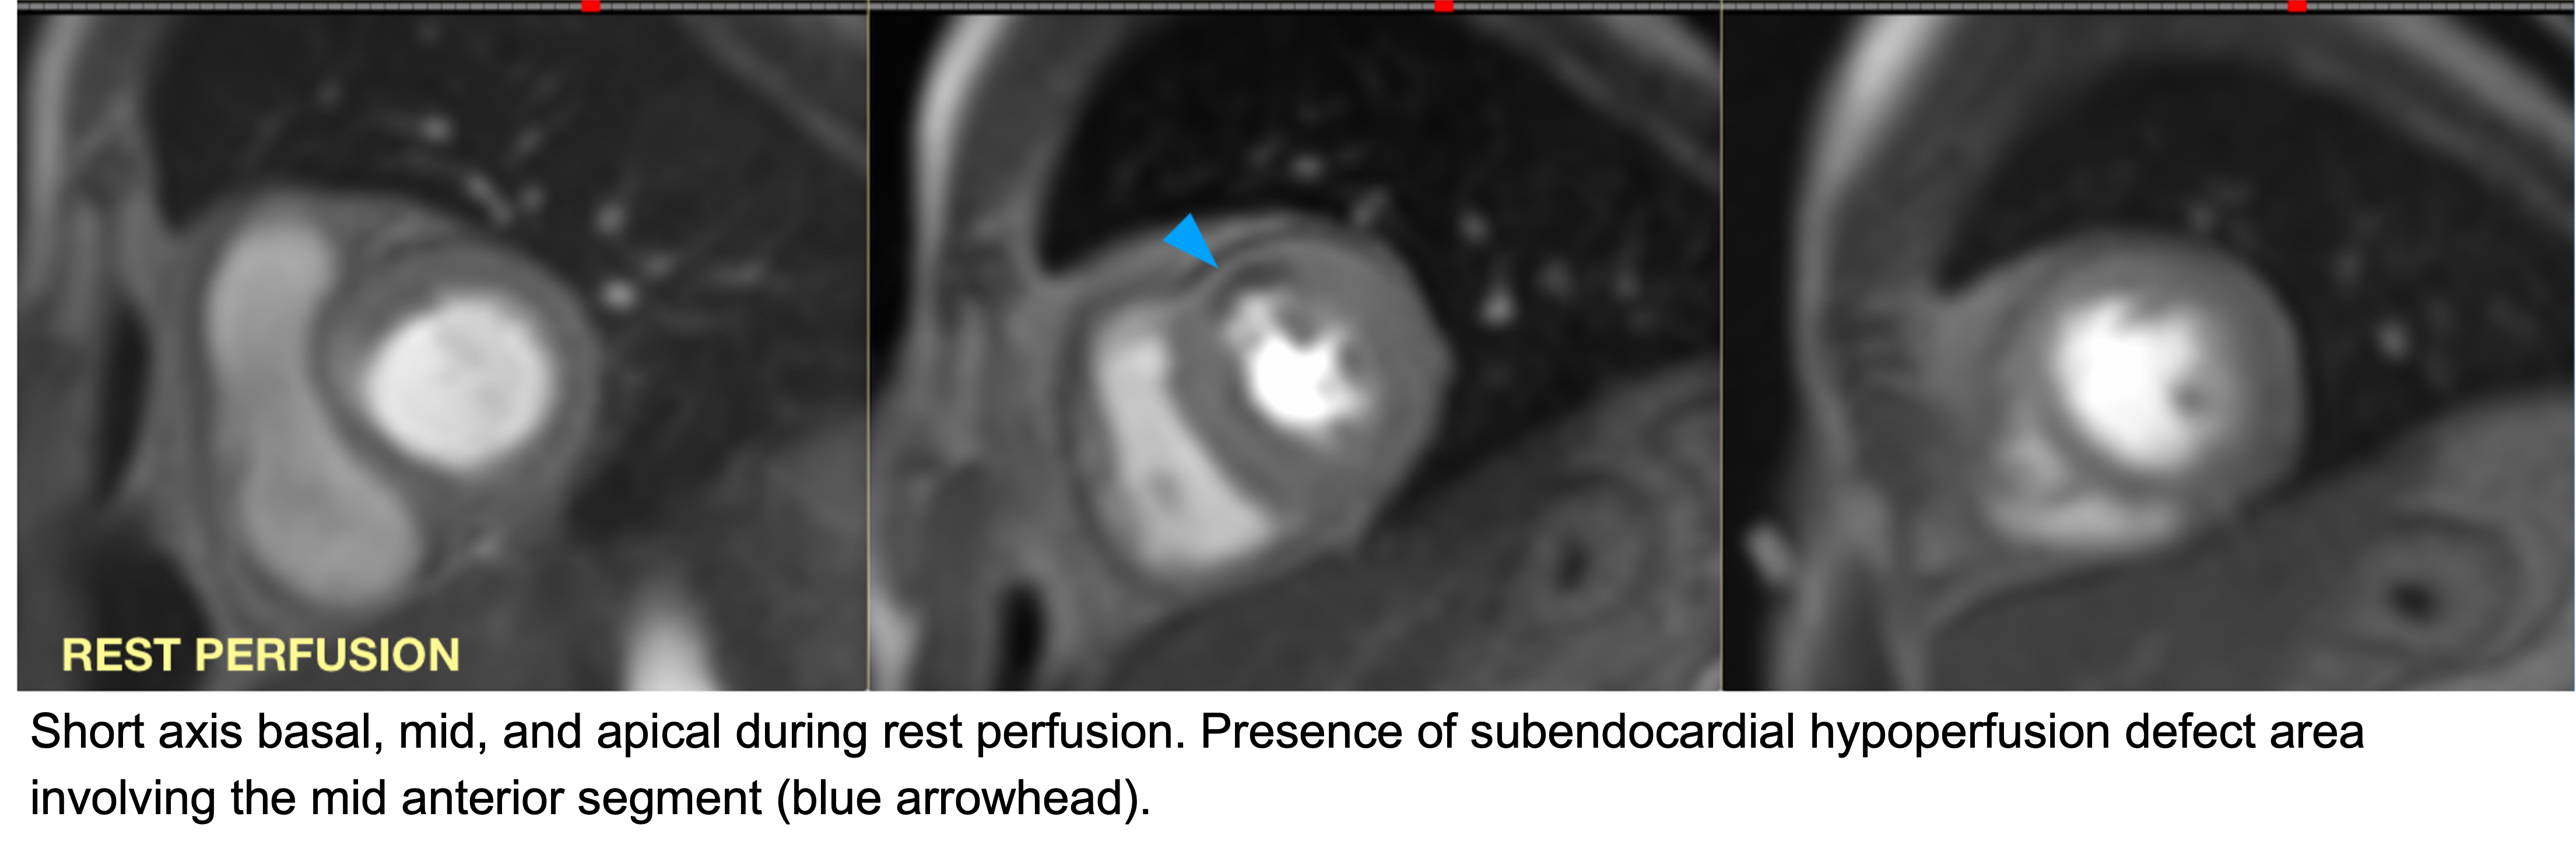

Cardiac magnetic resonance imaging (CMR): rest perfusion CMR demonstrated a mid-anterior hypoperfusion defect, consistent with adenosine-induced coronary vasospasm.

Our patient had severe angina with hypertensive urgency during adenosine stress cardiac magnetic resonance imaging (CMR), which resolved with supportive care. Adenosine is a potent coronary vasodilator commonly used in stress CMR and fractional flow reserve (FFR) evaluation. While typically safe, paradoxical coronary vasospasm is an uncommon but significant event, particularly in patients with endothelial dysfunction or variant angina. Proposed mechanisms include rebound vasoconstriction, sympathetic activation, and impaired endothelial response. Recognition is challenging as symptoms may mimic acute coronary syndrome, yet rapid identification and treatment are crucial to avoid adverse outcomes.